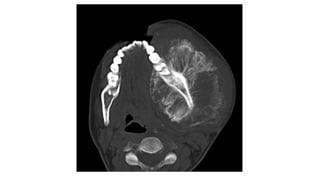

osteoma

🠶An isa benign tumour consisting of dense bone. T

hey

may occur in the paranasal sinuses.